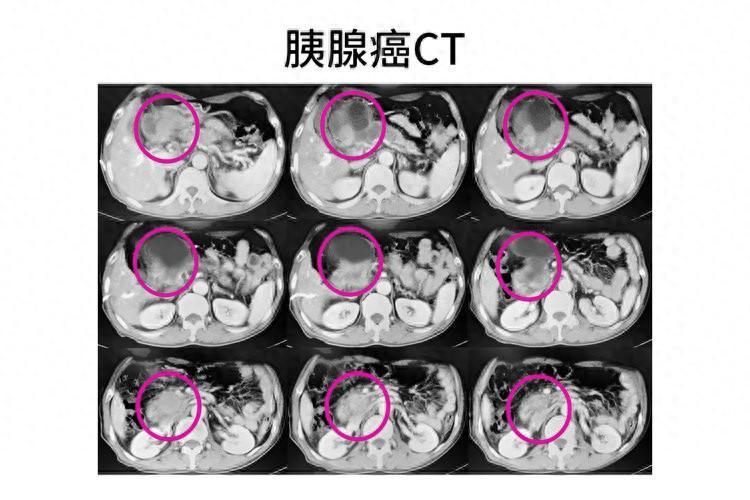

胰腺癌具有“三高”的特點,即發病率高、複發率高、死亡率高

很多患者一經確診就是晚期,手術切除率不到20%,確診後的患者平均生存率僅有3~6個月。故在臨牀上胰腺癌有“癌中之王”的稱號。